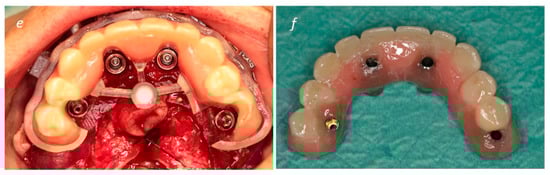

Description of the Technique